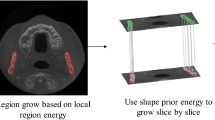

Methods Anonymous MR images data sets of the head from 12 subjects were subjected to a two-stage rule-constrained region growing approach to derive the shape of the body of the human mandible. An initial thresholding technique was applied followed by a 3D seedless region growing algorithm to detect a large portion of the trabecular bone (TB) regions of the mandible. This stage is followed with a rule-constrained 2D segmentation of each MR axial slice to merge the remaining portions of the TB regions with lower intensity levels. The two-stage approach was replicated to detect the cortical bone (CB) regions of the mandibular body. The TB and CB regions detected from the preceding steps were merged and subjected to a series of morphological processes for completion of the mandibular body region definition. Comparisons of the accuracy of segmentation between the two-stage approach, conventional region growing method, 3D level set method, and manual segmentation were made with Jaccard index, Dice index, and mean surface distance (MSD).